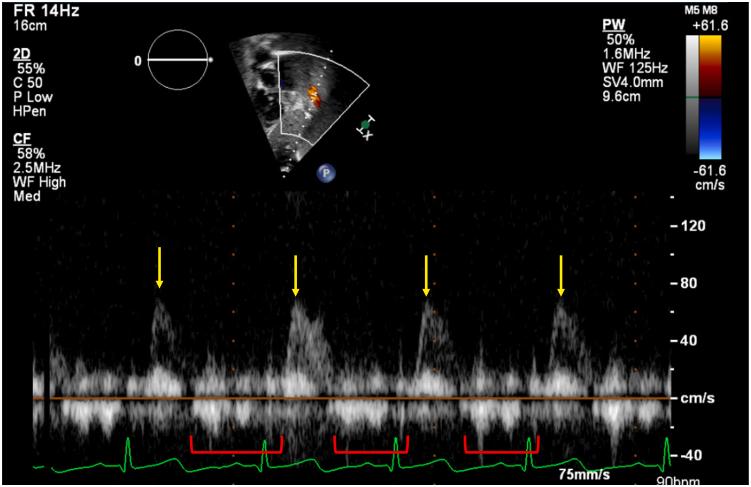

• Most AVFs present with a continuous murmur with radiation to the back. • There is little evidence to guide management of thoracic AVF. • Management options include surgical repair, embolization, or conservative management. • Conservative management is a reasonable approach in asymptomatic patients.